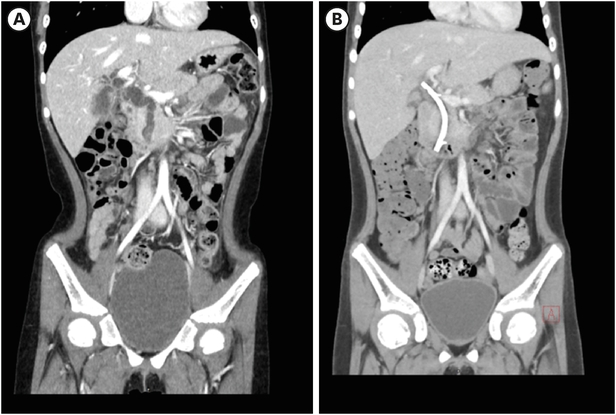

A 7-year-old girl visited the pediatric department of Asan Medical Center for endoscopic retrograde cholangiopancreatography (ERCP) to remove a distal common bile duct (CBD) stone. She was previously healthy and visited a nearby hospital due to abdominal pain and vomiting lasting for 13 days, and jaundice progressed the day before hospital visit. Computed tomography (CT) revealed tortuous dilatation of the extrahepatic bile duct abruptly narrowed in the distal CBD level with several distal CBD stones and anomalous pancreaticobiliary ductal union (APBDU, P-C type). The common channel was measured as 1.9 cm in length. These findings suggested type I CC related to APBDU. Secondary cholecystitis, cholangitis, and pancreatitis were additionally found (Fig. 1A). The same findings were confirmed on magnetic resonance imaging (Fig. 1B). After failure of the first ERCP at the previous hospital, she kept non per oral for one week, but symptoms and lab findings were never relieved (Table 1). So, she was determined to transfer to Asan Medical Center. ERCP was performed. Both pancreatic and CBD were successfully cannulated, and a 10 Fr. Endoscopic retrograde biliary drainage stent was retained in the bile duct for remnant stone excretion. No residual stone was found in follow-up CT in 3 days post ERCP (Fig. 2). Serum levels of liver enzymes, bilirubin, and amylase/lipase decreased to the normal range. Two months later, robotic CC excision and Roux-en-Y hepaticojejunostomy were performed. Severe adhesion and fibrosis around the CC reflecting chronic inflammation were noted. Type I CC was identified, and CBD was resected proximally above the cystic duct and distally at the upper border of the pancreas head. The patient recovered without acute complications. In ultrasonography of post-operative day (POD) 7, no abnormal finding was observed except a small fluid collection around hepaticojejunostomy. She was discharged on POD 9. In the permanent biopsy, edematous mucosal change of gallbladder (GB) and cystic duct was observed, but the diameter of the cystic duct was within the normal range (0.4 cm). In microscopic findings, papillary hyperplasia was identified. The resected CC was 2 cm in length and 2 cm in the widest circumference. It was pathologically confirmed as a CC, accompanying fibrosis and wall thickening changes of CBD, and low-grade BilIN was identified from the resected CC (Figs. 3 and 4). Papillary hyperplasia in GB suggests chronic inflammation in the biliary system due to CC such as BilIN. There was no involvement in the cystic duct and GB as in Type VI.

Fig. 2

Computed tomography follow-up after endoscopic retrograde biliary drainage insertion. (A) 3 days and (B) 7 days post procedure. Improved bile duct dilatation was observed.